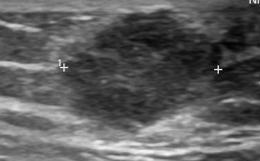

Υπερηχογράφημα ανδρικού μαστού. Πορογενές καρκίνωμα (Ευγενική παραχώρηση Dr. V. Penopoulos)